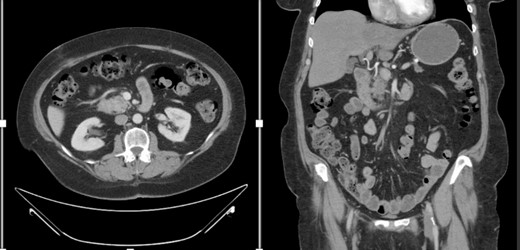

A female in her 60s presented with a 6-month history of progressive abdominal cramping, acholic stools, early satiety, post-prandial loose stools and flatulence. She reported a history of newly diagnosed diabetes mellitus with progressively difficult-to-control hyperglycemia requiring initiation of GLP-1 agonist therapy within the preceding year. She was a former cigarette smoker with 15 pack years’ history and no reported other substance use history. Basic hematological test was normal. Colonoscopy done showed no significant findings. A CT abdomen and pelvis with contrast identified a hypodense 1.5-cm solid mass in the pancreatic head with abutment of the superior mesenteric vein without arterial abutment or regional lymphadenopathy (Fig. 1); proximal main pancreatic duct dilatation and pancreatic parenchymal atrophy in the neck, body and tail. An endoscopic ultrasound identified a 2.8-cm hypoechoic partially circumscribed 1.5-cm mass in the pancreatic head. Core biopsy demonstrated poorly differentiated adenocarcinoma (PanKeratin, S100p, DOG-1, CK-7 positive; Ki67 20–30%). A staging CT chest and pancreatic protocol demonstrated an interval increase of the solid pancreatic head mass to 2.5 cm without other abnormalities (Fig. 1). Baseline serum Cancer Antigen 19-9 was non-elevated (3.02 U/mL). She was staged as a cT2N0M0 (Stage IB) pancreatic adenocarcinoma prior to therapy. Germline genetic testing demonstrated variants in KRAS, CDKN2A and TP53 with variant allele fraction of 25, 24.85 and 20.3%, respectively. Microsatellite instability was stable with a tumor mutation burden of 3.2 m/MB. She was initiated on pancreatic enzyme replacement therapy with resolution of her presenting symptoms and glycemic control was achieved with GLP-1 agonist therapy. The patient was referred for Genetic counselling.

CT abdomen and pelvis with IV contrast with axial and coronal views demonstrating the Pancreatic mass.